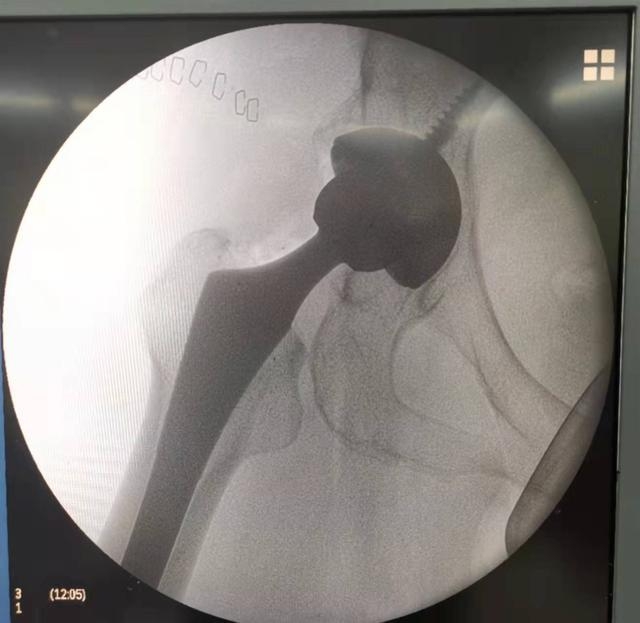

家住尚湖镇的朱师傅今年70岁,双膝关节反复疼痛多年,近两个月来愈加严重,步行上下楼梯时疼痛加剧,严重影响日常生活。近日,朱师傅在医生建设下,完成左膝关节置换术。令他意外的是,这次换关节的费用为8000余元,相比原先近3万元,降幅明显。

多年来,人工关节费用居高不下,让许多患者及家属望而却步。4月20日起,国家组织人工关节集中带量采购中选结果在浙江正式落地实施。这是继心脏冠脉支架之后,第二类国家级高值医用耗材集中带量采购。集采中选价格执行后,人工关节价格平均下降约75%,价格从“万元区”降至“千元区”,大大降低患者经济负担。为保障患者利益,磐安县紧跟政策、认真落实,在把好关键环节、衔接配套政策上发力,同步执行关节集采价格。